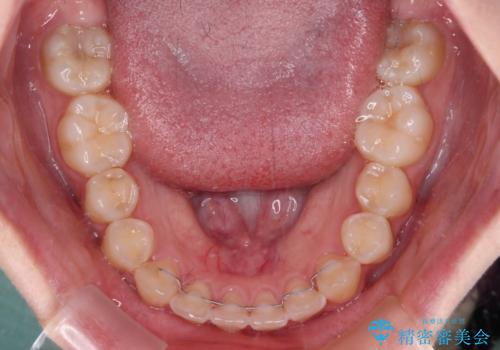

外側を向いていた奥歯は比較的早い時期に歯列に収まり、咬み合わせも磨きやすさも改善することができました。

歯列は元々悪くなかったので、1年ほどで治療を終えることができました。